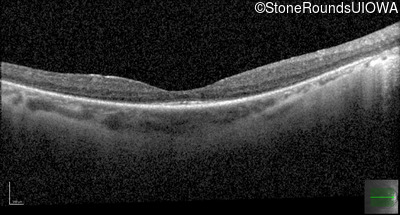

Optical Coherence Tomography - Right - 20/30 +2

Exemplar / OCT Stack